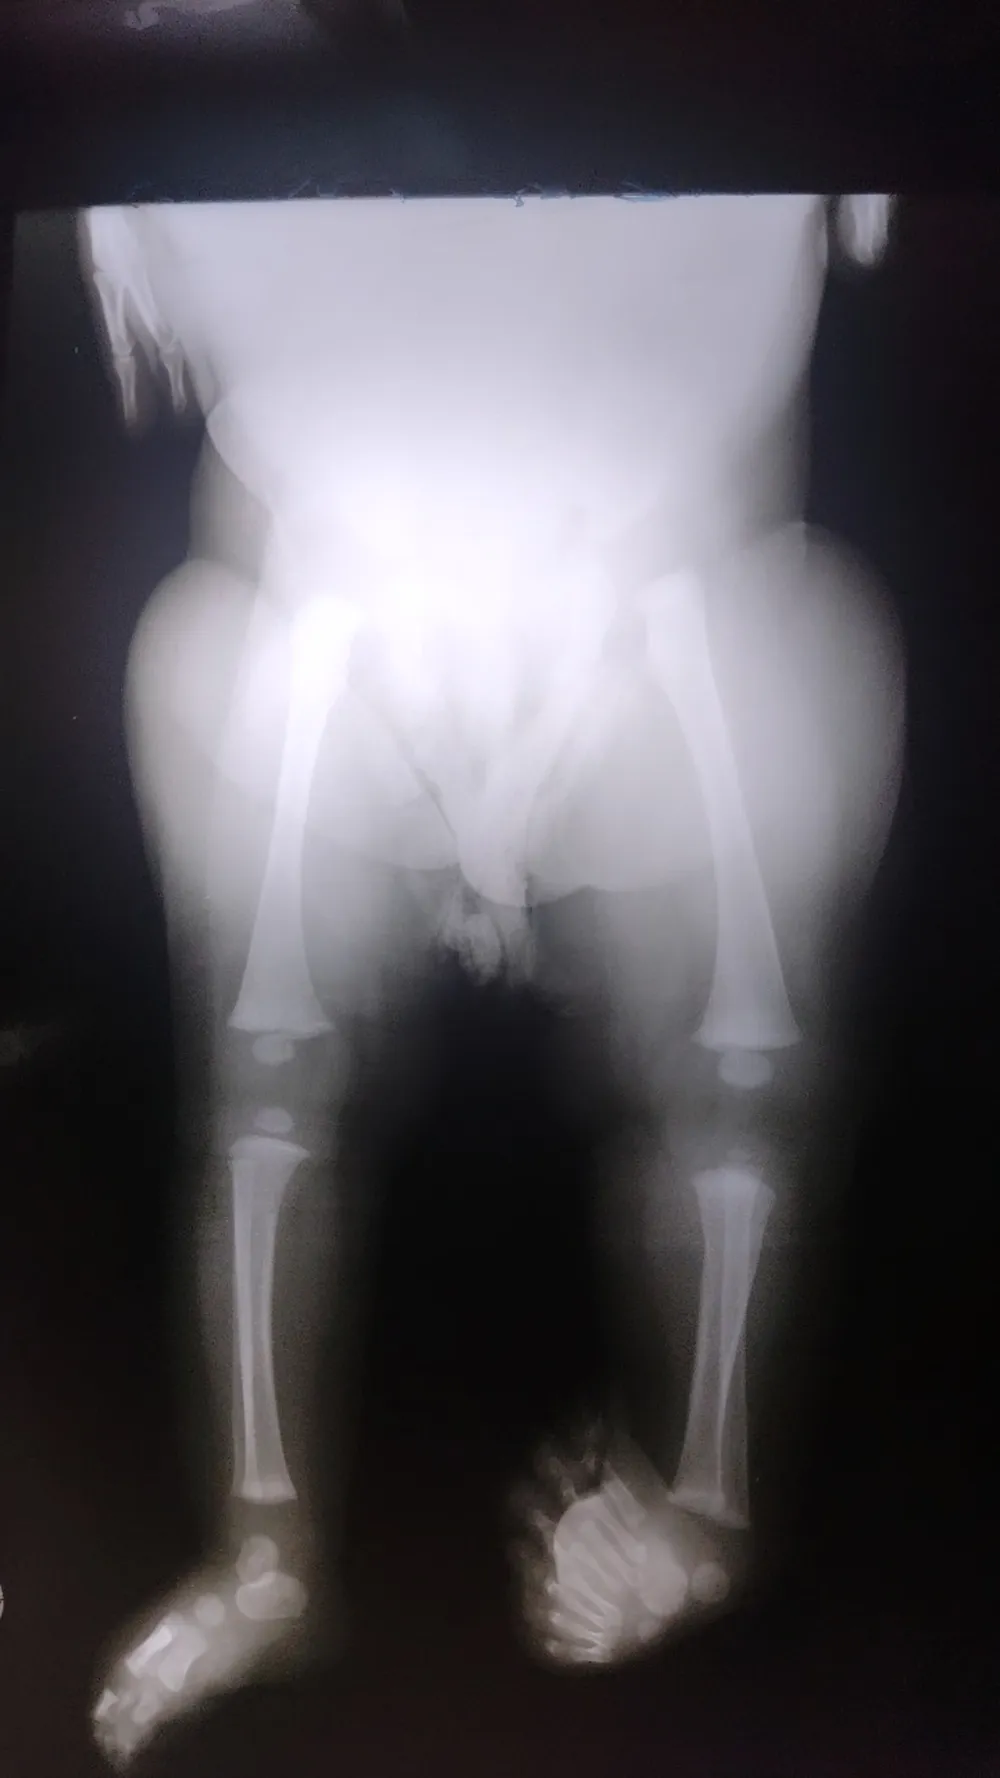

itoria Costa de Jesus tem 11 meses e nasceu com oito dedos no pé esquerdo. Segundo especialistas, a condição é extremamente rara e só acomete uma pessoa a cada dois milhões.

A bebê Vitoria Costa de Jesus, de 11 meses, que mora com a família em Rondonópolis, nasceu com oito dedos no pé esquerdo e uma deformidade que deixa o membro torto, como uma ‘duplicação’. Segundo a mãe, Priscila Costa de Jesus, devido à condição, a menina não consegue andar e nem ficar em pé por muito tempo, porque sente dor.

Segundo o mestre em cirurgia e metabolismo, Miguel Aprelino Alito, a menina tem duplicação e deformidade congênita no pé esquerdo, ou seja, a anormalidade ocorreu durante a gestação.

“O caso dela é extremamente raro. Além da grande quantidade de dedos, ela ainda tem a deformidade congênita, que deixa o pé torto e dificulta o andar dela, o que dificulta ainda mais o caso”, explicou.

Miguel disse que a única solução é realizar uma cirurgia que retire parte do pé dela, pois só assim ela conseguirá andar sem maiores dificuldades.

“O pé dela é muito largo, fica difícil até de calçar um sapato ou achar um que caiba no pé. Além disso, ainda é capaz que ela tenha feridas e calosidade”, disse.